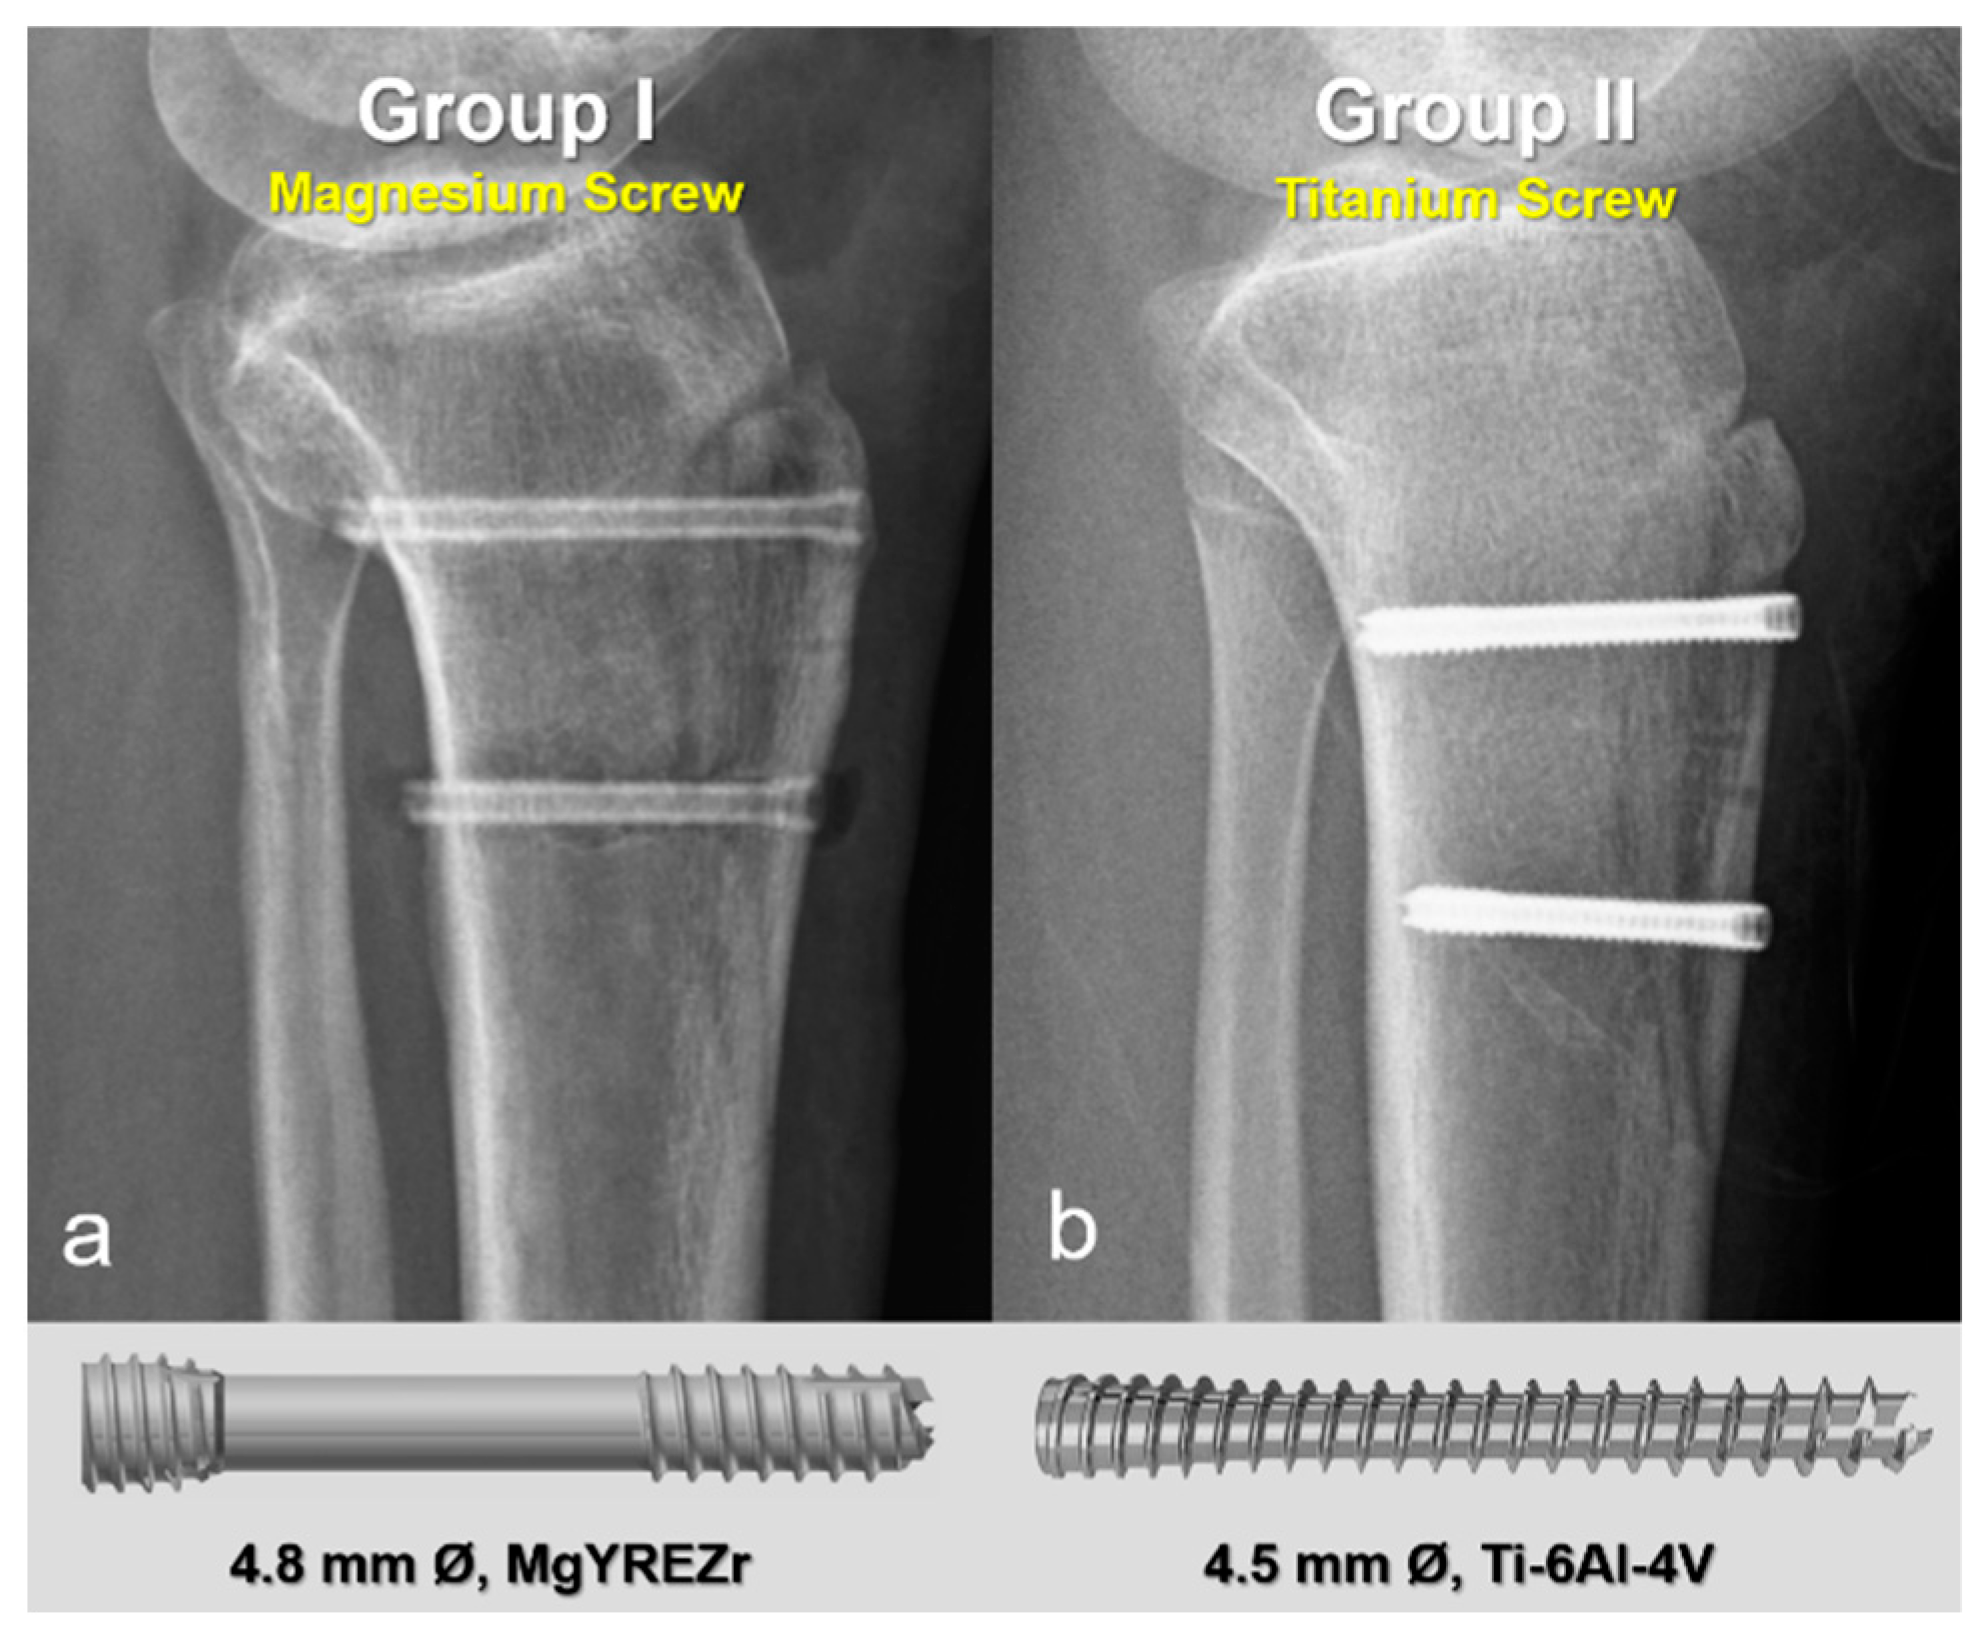

2.2. Surgical Technique and Implants